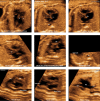

Diagnostic ultrasound (DUS) is, arguably, the most common technique used in obstetrical practice. From A mode, first described by Ian Donald for gynecology in the late 1950s, to B mode in the 1970s, real-time and gray-scale in the early 1980s, Doppler a little later, sophisticated color Doppler in the 1990s and three dimensional/four-dimensional ultrasound in the 2000s, DUS has not ceased to be closely associated with the practice of obstetrics. The latest innovation is the use of artificial intelligence which will, undoubtedly, take an increasing role in all aspects of our lives, including medicine and, specifically, obstetric ultrasound. In addition, in the future, new visualization methods may be developed, training methods expanded, and workflow and ergonomics improved.